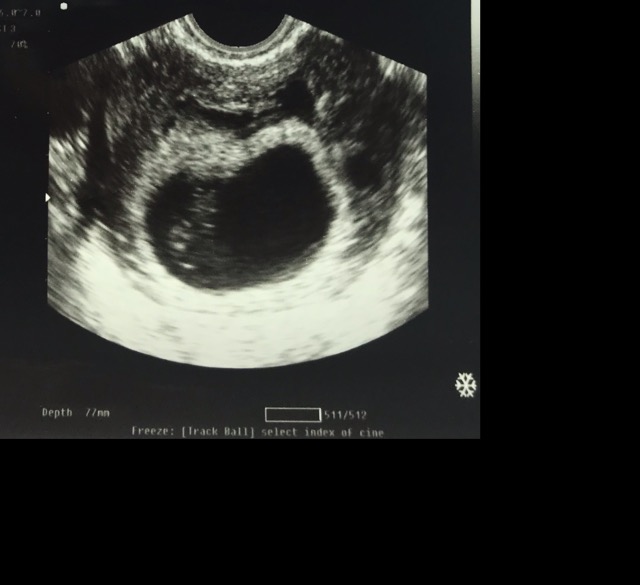

Boy or girl according to the Ramzi theory?

I had my 13 week and 2 day ultrasound on Friday and baby was measuring 14 weeks. I’m wondering if my baby is a boy or a girl. The heartbeat was 155. The previous ultrasound was from my 8 week scan.